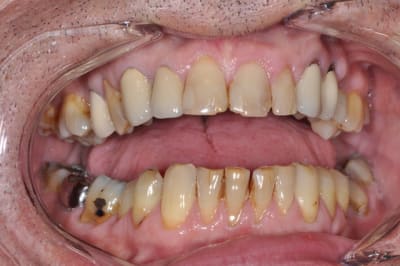

ce patient a une demande essentiellement esthétique,

Pas du tout d'accord : je suis même choqué de ces réponses. Le patient se fiche de ses dents du bas et s'intéresse aux incisives sup. Ne pas restaurer les dents du bas n'a strictement aucune importance sur le plan médical, donc pourquoi en rajouter.

Pour les 3 antérieures, je proposerais 3 couronnes in céram ou e max. Il faut voir ce que les patients demandent et pas devenir un obsédé compulsif de la perfection.

effectivement pour le bas traitement à minima,

éclaircissement en cours puis réalisation de composites proximaux,

Pas mal les photos mais on pourrait avoir des vrais photos de sourire pour comprendre comment le patient se voit.

la réalisation d'un traitement global prothétique ou d'ortho se tient au regard de l'affaissement occlusal du bloc postérieur, l'occlusion plus ou moins foireuse de ton patient risque de le placer devant un pronostic esthétique moyen à long terme, c'est déja le cas au niveau 23 et 24, donc se contenter de 12 à 22 me parait léger. Mais bon le terme esthétique est tellement floue!

il est complexé par ses dents de devant depuis de nombreuses années ( il a 58 ans )

son souhait n'est pas d'avoir la bouche parfaite mais de pouvoir sourire.

OK on y voit plus clair, si on prend l'image comme une référence, ce qui me choc autant que le bloc antérieur d'un point de vue esthétique (et là encore c'est une vision subjective donc à faire valider au patient d'abord), c'est la position de 14, 15 ,16, ingressées suite à affaissement occlusal, oui je sais c'est fonctionnel, mais c'est moche aussi!!!!

Ensuite sérieusement les CCM en place font toc, c'est aussi moche, encore une fois ce contenter de 12 à 22 me semble léger, même si dans le shèma du sourire "vrai" l'esthétique de la gencive est tout d'un coup devenue secondaire.

Alors ce battre pour savoir si on fait des couronnes ceramoceram ou des 3/4 ou des facettes, alors que le reste ne ressemble à rien, n'a plus trop de sens non?